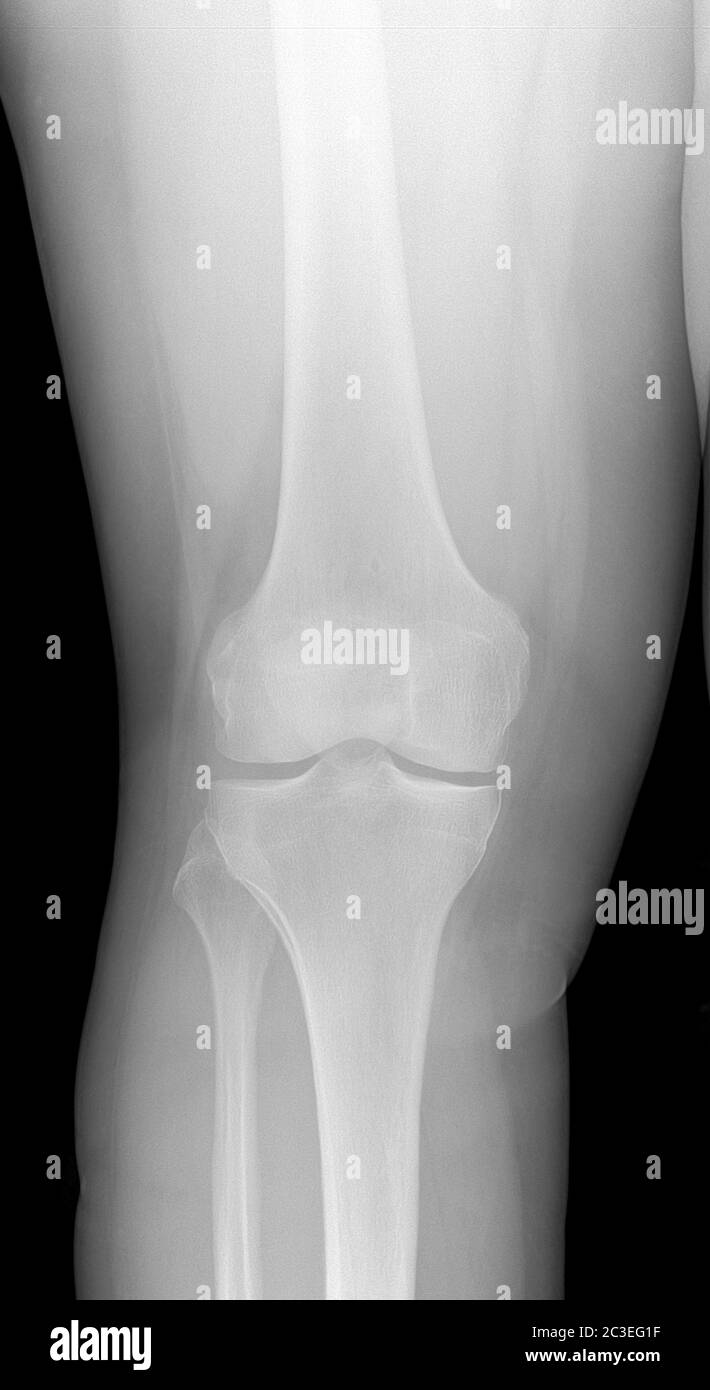

Normal radiographic anatomy of the knee 2 Distal femoral metaphysis

Image Of Knee XRay. Detecting Radiographic Knee Osteoarthritis Radiographic Knee the most common injuries involve the soft tissues, including ligaments, cartilage, and menisci. although the cornerstones of imaging evaluation of the knee are radiographs and magnetic resonance (mr). radiography and ct scanning remain the primary imaging modalities for detection of osseous injuries about the knee, but mri has taken center. the anatomy and pathologic conditions of. Radiographic Knee.

Radiographic knee anatomy and OA feature locations. Download Radiographic Knee the anatomy and pathologic conditions of the anterior knee can be approached systematically by. although the cornerstones of imaging evaluation of the knee are radiographs and magnetic resonance (mr). the knee series is a set of radiographs taken to investigate knee joint pathology, often in the context of trauma. radiography and ct scanning remain the primary. Radiographic Knee.